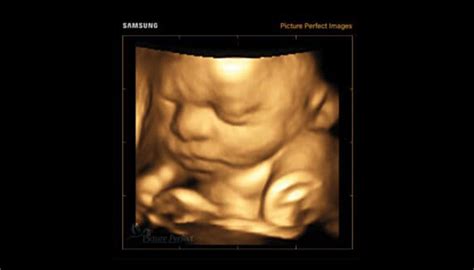

Ecografia 3D și 4D reprezintă tehnologii avansate de imagistică utilizate în timpul sarcinii pentru a oferi imagini detaliate ale fătului. Ecografia 3D utilizează ultrasunetele pentru a crea imagini tridimensionale ale fătului. Astfel, se obține o imagine mai clară a structurilor anatomice fetale. Ecografia 4D este o formă avansată de ecografie 3D, care adaugă elementul de timp, oferind imagini în mișcare în timp real. Practic, ecografia 4D creează un video al fătului în mișcare, permițând observarea expresiilor faciale și a activităților fetale în direct.

Este important de menționat că imaginile detaliate furnizate de ecografiile 3D/4D pot ajuta medicii să planifice intervenții medicale prenatale sau postnatale necesare. Acestea oferă o înțelegere mai bună a problemelor medicale, astfel că simplifică procesul de diagnostic. În plus, prin intermediul ecografiei 3D sau 4D, conexiunea dintre părinți și făt se consolidează. Este foarte important pentru părinți să-și vadă mai bine copilul, această procedură oferindu-le o oportunitate unică de a se conecta emoțional cu fătul lor înainte de naștere.

Ecografia 3D este o metodă imagistică medicală folosită în mod frecvent în examinări fetale, cardiace, transrectale și intravasculare. La fel ca ecografia bidimensională (2D), cea 3D folosește unde sonore de înaltă frecvență, dar necesită sonde/transductori de volum și un software special care va realiza o reconstrucție 3D a structurilor, organelor și, în cazul bebelușului, a sistemului osos. În cazul gravidelor, ecografia 3D se poate propune pacientelor care doresc să aibă imagini mai clare cu trăsăturile faciale ale fătului. Procedura se efectuează între săptămânile 22 și 32, ideal între 25-28 de săptămâni.